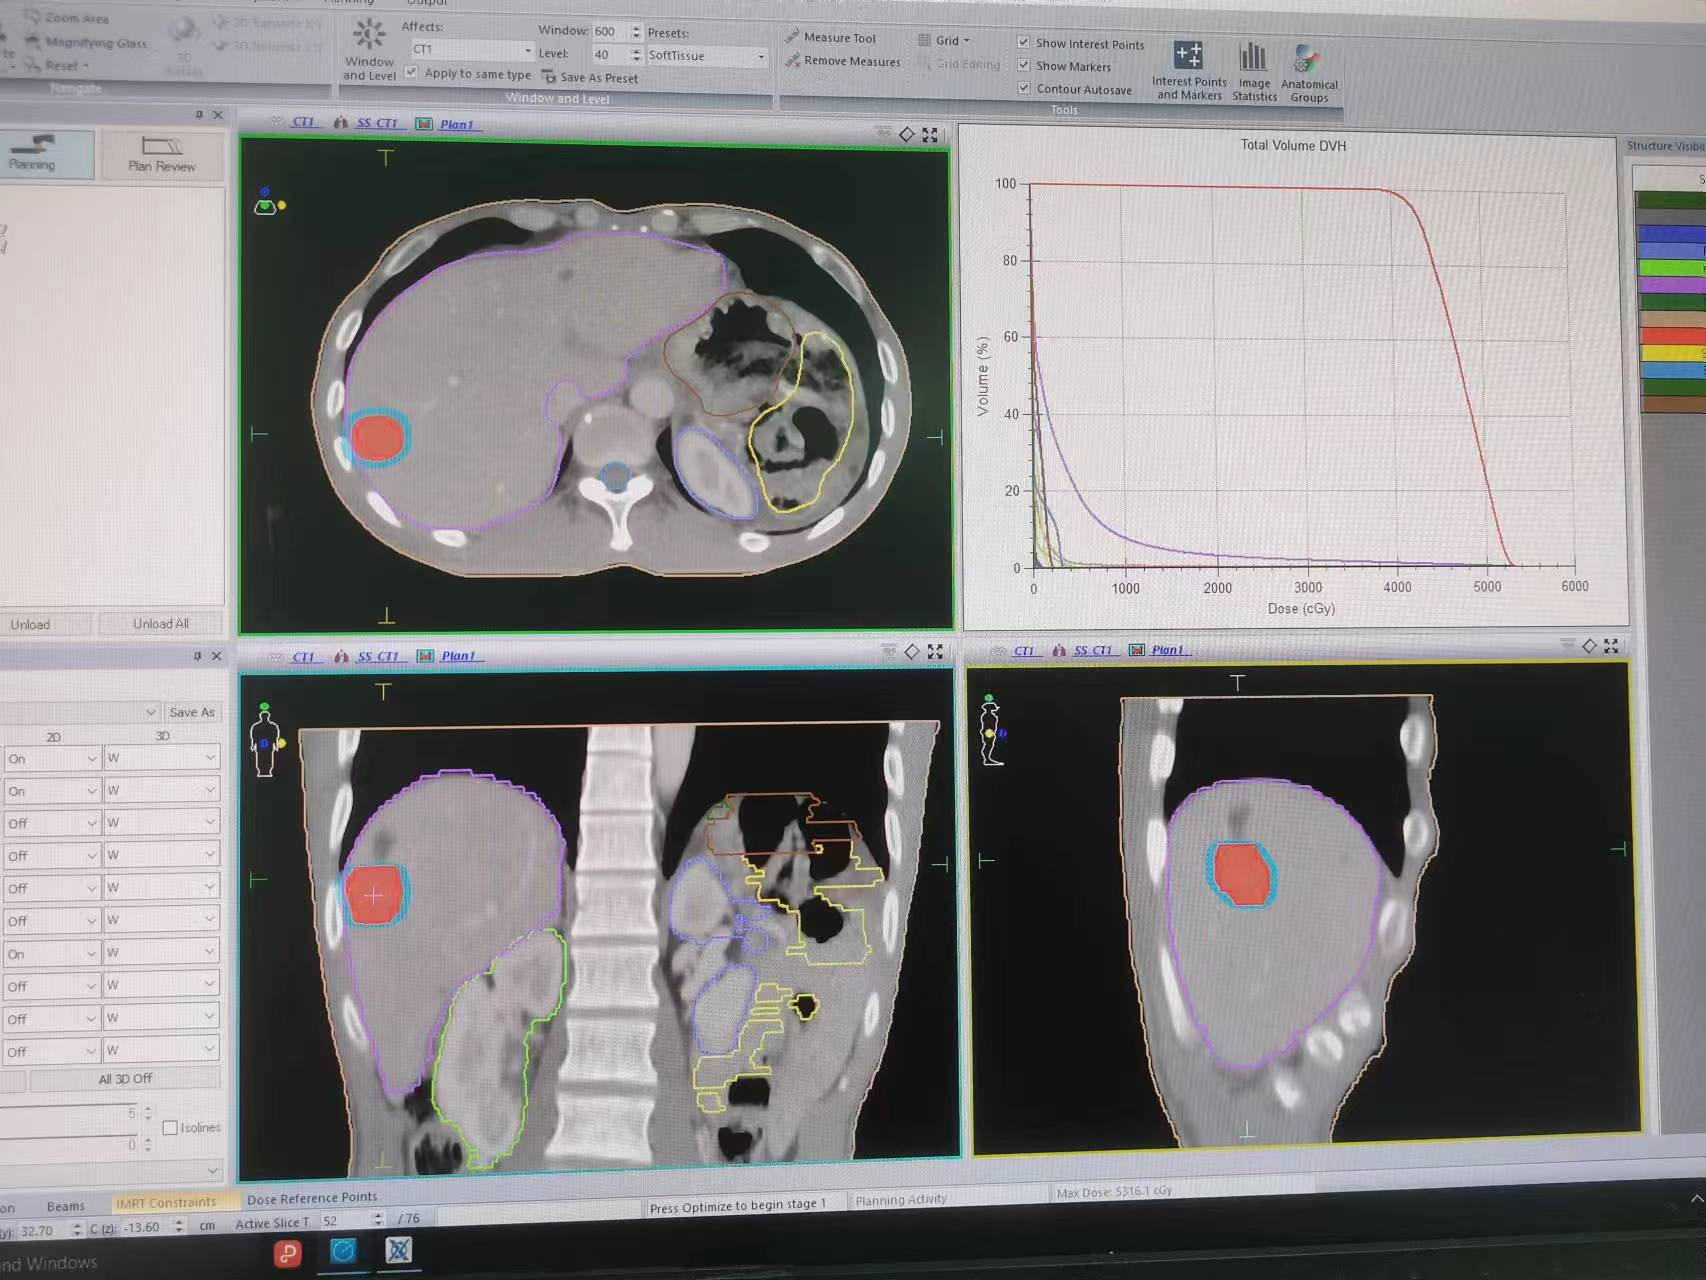

3. 将CT扫描得到的图像导入治疗计划系统,由医生勾画靶区及确定放射治疗方案。物理师制作放射治疗计划后经医师审核批准后传至治疗服务器待用。

2.肝脏肿瘤及肝转移病灶,孤立性或小于3个以内,肿瘤小于5cm的SBRT(X刀)放射治疗SBRT放射治疗。目的是缩短治疗流程、提高肿瘤靶区剂量、增加治疗疗效,降低放射性肝损伤及胃肠副反应。

1.肺部肿瘤及肺转移病灶孤立性或小于3个以内,肿瘤小于5cm的SBRT(X刀)放射治疗。目的是缩短治疗流程、有效提高恶性肿瘤的局部治愈率,同时明显降低放疗并发症,减小肺纤维化副反应。